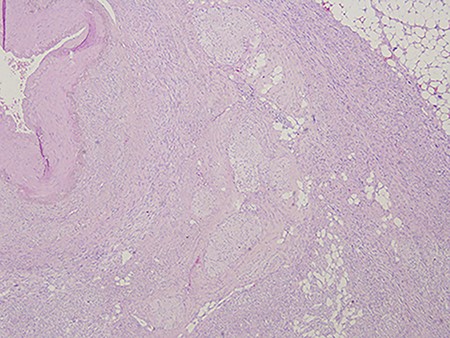

Pathological examination of the surgical specimen confirmed the diagnosis of A-LMS arising from the mesenteric artery also infiltrating the SMV, characterized by foci of coagulative necrosis, immunoreactivity for myogenic markers (smooth muscle actin and desmin, and negativity for S100, C-kit and CD 34), a low number of mitosis (5–10 ×10 HPF) and an high proliferative activity (Ki67) of the tumour cells (30%) (Fig. 5).

Arterial leiomyosarcoma originating from the superior mesenteric artery; notice the nuclear pleomorphism, mitotic figures and necrotic areas typical of a leiomyosarcoma.